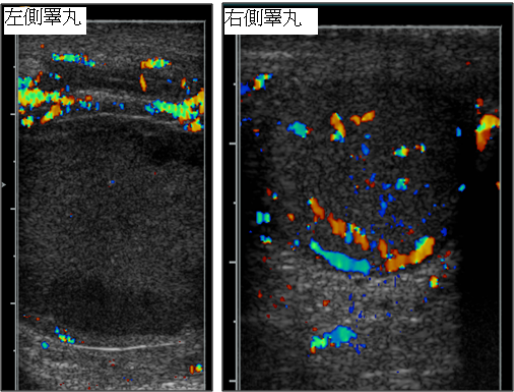

66.10歲男孩突然陰囊劇痛,睪丸彩色超音波掃描如下圖,最正確的診斷為下列何者?

(A)右側之睪丸發炎 (B)左側睪丸扭轉 (C)右側睪丸腫瘤 (D)左側睪丸腫瘤